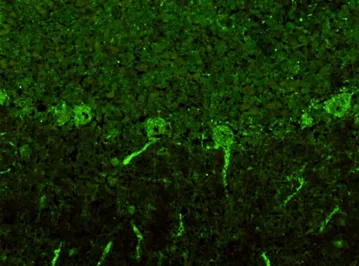

• Ядрышковый нейрональный тип свечения

Ядрышковый нейрональный тип свечения

Характеризуется специфическим точечным свечением ядрышек нейрональных клеток и встречается у пациентов с Ma1 и Ma2/Ta антителами.

• Ядрышковый нейрональный тип свечения чаще всего выявляется у пациентов со стволовым энцефалитом, лимбическим энцефалитом и ассоциирован с такими заболеваниями, как мелкоклеточная карцинома легких, карцинома яичка и карцинома молочных желез. Наиболее часто данный тип свечения встречается при наличии Ma1, Ma2/Ta антител.